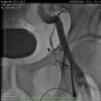

A 51-year-old white man with a history of hypertension and tobacco abuse and a strong family history of premature coronary artery disease was initially admitted to our hospital with worsening chest pain and underwent pharmacological stress testing, which showed distal anterior and apical wall ischemia with preserved left ventricular systolic function. He was referred for coronary angiography, initially performed using a 6F system and right femoral artery access. A 95% lesion of the left anterior descending artery with thrombus was stented without complications. He continued to have chest pain and a second intervention via the left groin was performed four days later on a 80–90% stenosis of the mid right coronary artery (RCA) and 80% stenosis of the mid posterolateral ventricular branch (PLV). During the procedure a 0.035inch wire and 6F sheath were advanced without difficulty. The RCA was engaged with a 6F Amplatz Left (AL) 0.75 guiding catheter (GC) (Cordis, Miami Lakes, FL) for better back-up and a 0.014inch Balance Middle Weight (BMW) wire was advanced to the distal PLV without difficulty. Both lesions were predilated with a 3.0mm×12mm compliant balloon and 3mm×15mm Vision and 4.5mm×18mm Ultra stents were placed in the PLV and mid RCA, respectively, without difficulty and with an optimal result (Figures 1 and 2). During the last cineangiogram, with the BMW wire inside the guide but outside the coronary artery, the AL GC became disengaged. We attempted to reengage the RCA but were unsuccessful, and could not transmit torque through the GC. Fluoroscopy revealed kinking of the distal GC in the external iliac artery. During attempts to straighten the GC by counterclockwise rotation, the guiding catheter fractured into two pieces (Figure 3). The proximal broken piece came out with the sheath and manual pressure was applied. The BMW wire was still firmly attached to the guide. An 8F arterial sheath was then introduced partially up the broken GC over the BMW wire, the introducer sheath was removed, and attempts were made to advance a loop snare next to the kinked GC, with no success, and to advance a 0.035inch J-tip wire next to the GC, also without success. At this time, the other option was to obtain access by the right femoral or brachial/radial artery to try to snare the proximal or distal end of the GC, but there were concerns because of the significant kink potentially traumatizing the exit vessel, especially with a brachial/radial approach. While we were considering advancing a 15-mm Amplatz gooseneck snare (ev3 Inc., Plymouth, MN) over the wire to snare out the distal fragment, it was decided to use the unusually firmly stuck BMW wire as an advantage and to pull back the wire while simultaneously advancing the 8F sheath over the GC. The BMW wire was pulled back rotating a hemostat in a counterclockwise direction and the sheath was advanced while clockwise rotation was applied, which enabled the GC to be straightened; we were able to withdraw the GC inside the sheath (Figure 4), then the sheath was pulled out with the GC inside. Although the distal portion of the fractured GC was out, we were still unable to remove the BMW wire (Figure 5); we therefore cut the guiding catheter proximal to the kink, removed the BMW wire and inserted a J-wire, removed the remaining GC and then reinserted the 8F sheath. The femoral angiogram showed tortuous iliac arteries with a small leak on the medial side of the sheath with no dissection or perforation (Figure 6). A FemoStop was applied at low pressure to stop the leak around the sheath, and the sheath was then removed once active clotting time was <150s. Hemostasis was achieved using manual pressure, and then a FemoStop was applied at low pressure for two more hours, followed by bed rest for a total of eight hours. The patient remained stable and asymptomatic throughout the procedure and overnight, and ambulated without difficulty the next day. The following day, before he was discharged, he went to the bathroom and had to strain, and subsequently developed acute left groin swelling and pain. Examination revealed a palpable hematoma suggestive of pseudoaneurysm. An ultrasound exam confirmed the existence of a 4.2cm×2.9cm pseudoaneurysm which was treated with ultrasound-guided compression. He was subsequently ambulating with no difficulty and was discharged home, and no new problems occurred during follow-up.

Unfortunately, in our patient a slight counterclockwise rotation fractured the GC. Part of the reason for this could be the three knots in the GC visible after it was withdrawn (Figure 5), suggesting multiple kink points in a highly tortuous iliac artery making multiple three-dimensional turns (Figure 6). This was probably also the reason for the BMW wire entrapment.